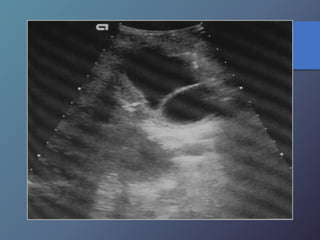

Abscesos Hepáticos Parasitarios

La infección hepática por entamoeba histolytica

es la manifestación más frecuente de amibiasis

extraintestinal

• Alrededor del 15% de los pacientes presentan diarrea

en el momento del DX.

• Son redondas u ovales.

• Ausencia de pared, hipoecogenicos en relación al

hígado.

• Ecos internos de nivel bajo, finos y continuidad con el

diafragma.

• Ubicados a nivel del lóbulo derecho

Abscesos Hepáticos Parasitarios Lainfección hepática por entamoeba histolytica es la manifestación más frecuente de amibiasis extraintestinal • Alrededor del 15% de los pacientes presentan diarrea en el momento del DX. • Son redondas u ovales. • Ausencia de pared, hipoecogenicos en relación al hígado. • Ecos internos de nivel bajo, finos y continuidad con el diafragma. • Ubicados a nivel del lóbulo derecho